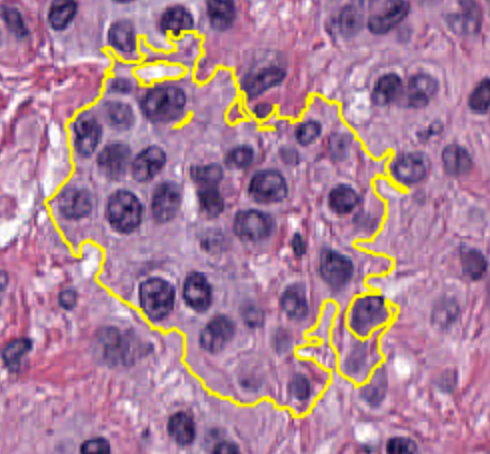

3-2:锁定与解锁

注释可以是一项费力的过程。因此,丢失或意外编辑注释可能会相当令人沮丧。

为了帮助降低这种风险,注释可以被锁定或解锁。您可以通过右键点击选定的注释来访问这个功能。

3-3:设置属性

注释也可以设置属性。从分析的角度来看,这些属性中最重要的通常是分类。但从显示的角度来看,还有名称和颜色属性。

您可以通过按Enter键快速为选定的注释设置这些属性。

名称可以在查看器中显示或隐藏,使用“View ‣ Show names”,或快捷键N。